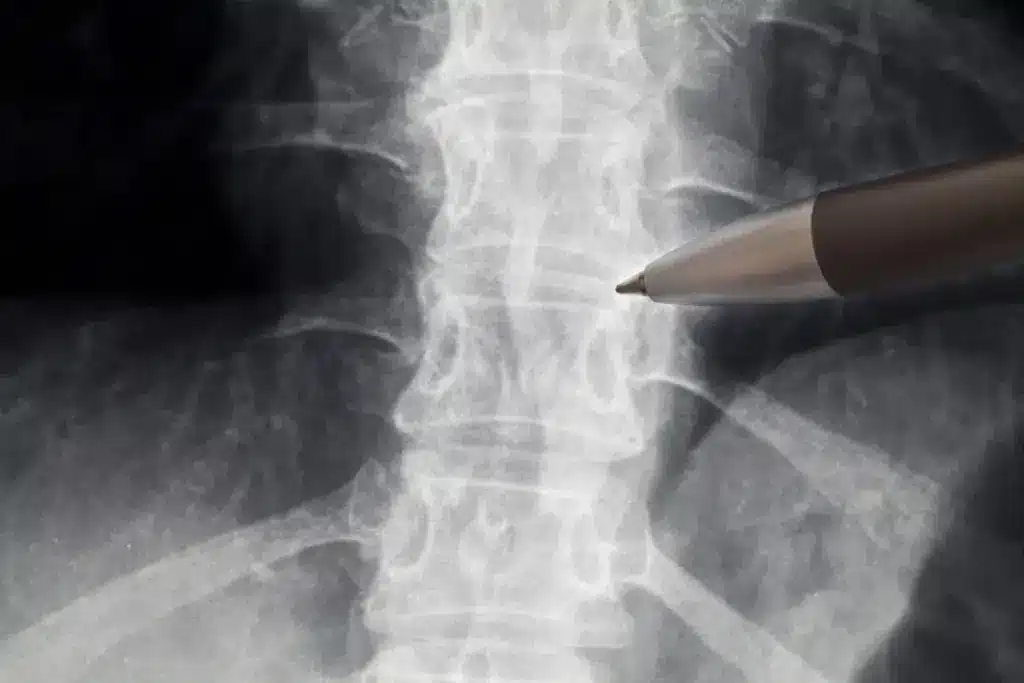

Diagnostic Approaches for Spine Degeneration

Diagnosing spine degeneration needs a detailed approach. We use advanced imaging and physical checks. This helps us find out how bad the degeneration is and plan the best treatment.

Imaging Technologies

Imaging is key in finding spine degeneration. We use different tools, like:

• Magnetic Resonance Imaging (MRI): MRI shows soft tissues well, like discs and nerves. It spots degenerative changes.

• Computed Tomography (CT) scans: CT scans show bones clearly. They help find degenerative changes like osteophytes.

• X-rays: X-rays check vertebrae alignment and spot degenerative signs, like disc narrowing.